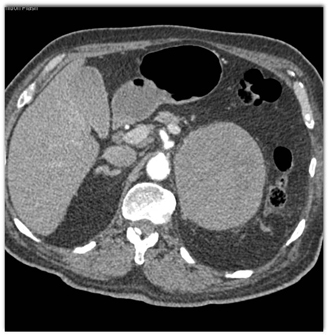

The most likely diagnosis in this case is

adrenal adenoma

pheochromocytoma

lymphoma

metastatic melanoma